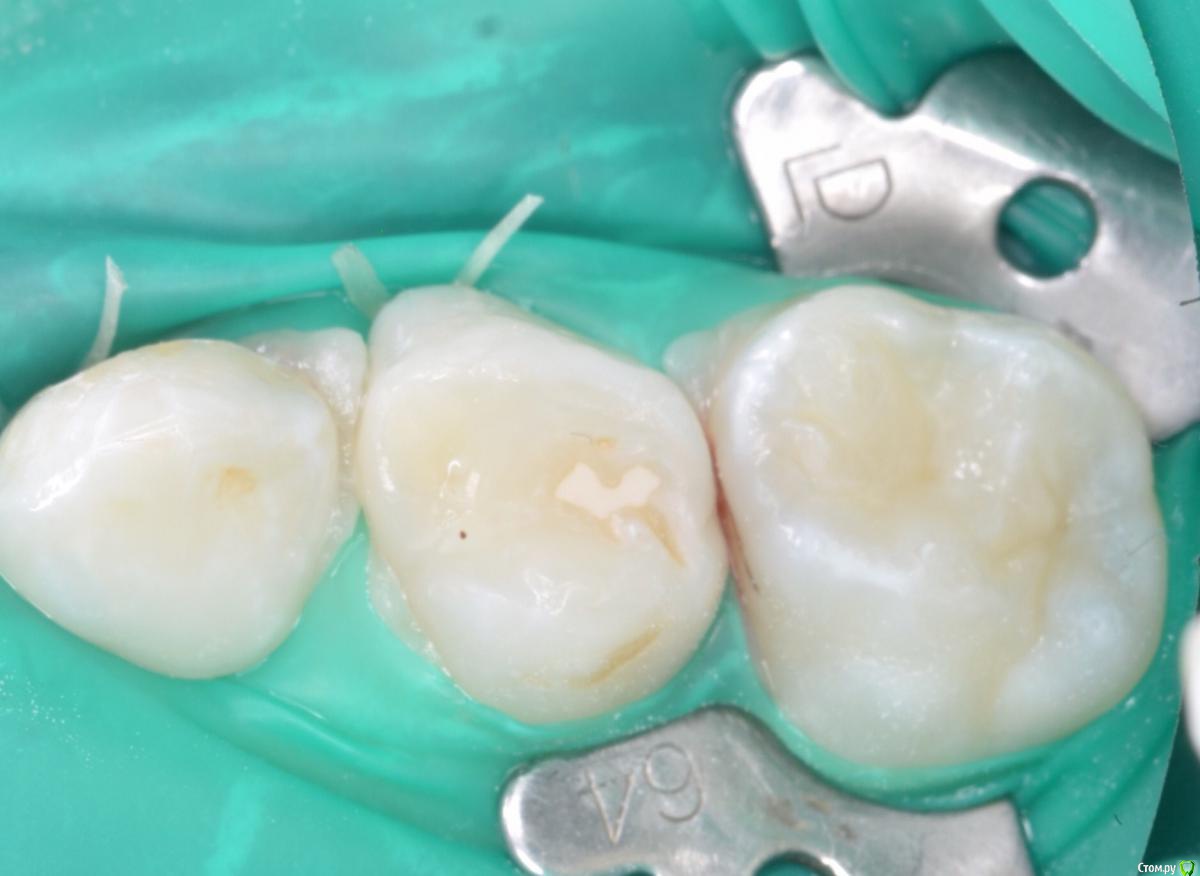

CRAZYDUCK Опубликовано 15 мая, 2018 Автор Поделиться Опубликовано 15 мая, 2018 Герметизация 3.6 и лечение кариеса 7.5. 1 Ссылка на комментарий

CRAZYDUCK Опубликовано 20 мая, 2018 Автор Поделиться Опубликовано 20 мая, 2018 Вовремя замеченный кариес не успеет превратиться в пульпит . Поверхностный кариес контактных поверхностей 6.5 и 6.4 зубов, подтверждённый RVG исследованием . Серёже 3,5 года , но он большой молодец , продолжительность 45 минут ( анестезия, коффердам , преп турбиной и рондофлекс , пломбирование и полировка. 1 Ссылка на комментарий